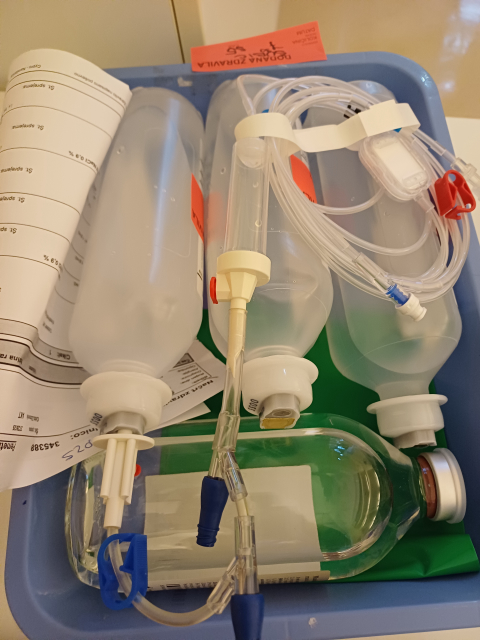

DIAGNOZA RAK/25/ Soba z razgledom

Kaj nam teče v žilo?